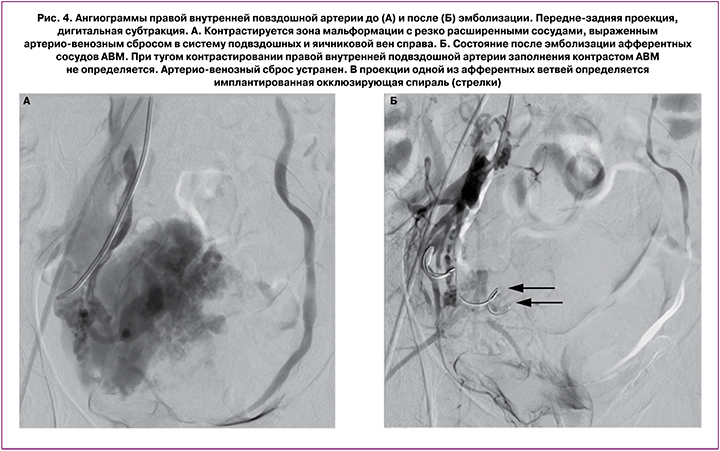

По результатам исследования проведена консультация ангиохирурга, выполнена технически успешная двусторонняя ЭМА, ветвей внутренних подвздошных артерий. Описание операции: под местной анестезией раствором новокаина пунктирована правая бедренная артерия. Установлен интродьюсер 5F. Катететром С2 катетеризирована правая почечная и правая добавочная почечная артерии. Выполнена ангиография. Отмечено кровоснабжение правой яичниковой артерии из измененных ветвей почечных артерий справа. Пупочный артериальный катетер проведен в левую и правую внутренние подвздошные артерии, выполнена ангиография. На ангиограммах отмечается контрастирование обширной зоны патологической васкуляризации в проекции малого таза. Питание осуществляется из маточной артерии слева, маточной артерии справа (определяется крупная артерио-венозная фистула с преимущественным сбросом контрастного препарата в подвздошные вены справа), ветвей внутренней подвздошной артерии справа. Выполнена ЭМА слева цилиндрическими эмболами, маточной артерии справа спиралью 14 см × 15 мм, ветвей внутренней подвздошной артерии справа цилиндрическими эмболами.

На контрольных ангиограммах кровоснабжение патологического сосудистого сплетения резко редуцировано. Катетер и интродьюсер удалены, компрессионный гемостаз, наложена асептическая давящая повязка. Использовано эмболизирующего материала: цилиндры (ААА 750 мкм × 10 мм) – 8 фл., цилиндры (ААА 600 мкм × 10 мм) – 1 фл. Эффективная эквивалентная доза: 1,37 мЗв. Использовано контрастного препарата: 600 мл (рис. 3, 4).